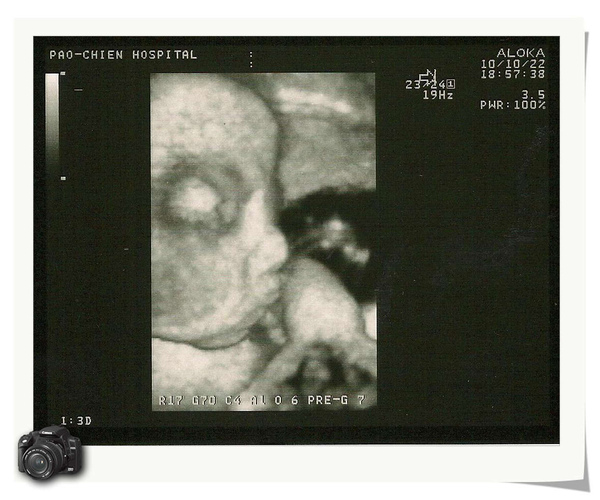

上週五去產檢,本來超級擔心我自己的體重暴增,小寶弟也過大,因為這兩週一直在趕報告、加班,就一直吃東吃西、喝飲料,吃到都覺得自己快變大胖子囉!結果還好還好,我增加1公斤,小寶弟2600G,醫生說有可能會提早一-二週生,看樣子小寶弟等不到辜把鼻回來囉!

眼睛看起來有沒有比翔baby大的感覺呀!小寶弟的"小弟弟",^^"leaf0817 發表在 痞客邦 留言(0) 人氣(32)